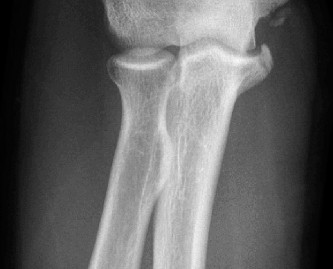

- Radiographs: AP, lateral, and oblique views of the elbow are essential to rule out avulsion fractures, loose bodies, osteophytes, and physeal injuries (in adolescents). Stress radiographs (gravity or manual) can objectively quantify valgus gapping but require expertise to perform and interpret.

- Magnetic Resonance Imaging (MRI): MRI, preferably with an arthrogram, is the gold standard for evaluating UCL integrity, flexor-pronator pathology, and associated intra-articular injuries (e.g., osteochondral lesions). A complete rupture will show discontinuity of the ligament, while a partial tear may show high signal intensity within the substance of the ligament. T2-weighted fat-saturated sequences are particularly useful.